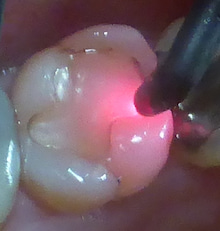

下の機械は

ダイアグノデント(ドイツ製)といいます。

虫歯をレーザーで調べるものです。

赤い光のレーザーを穴に当てます。

すると 32という値が出ました。

15以上は 何等かの治療が

必要と考えています。